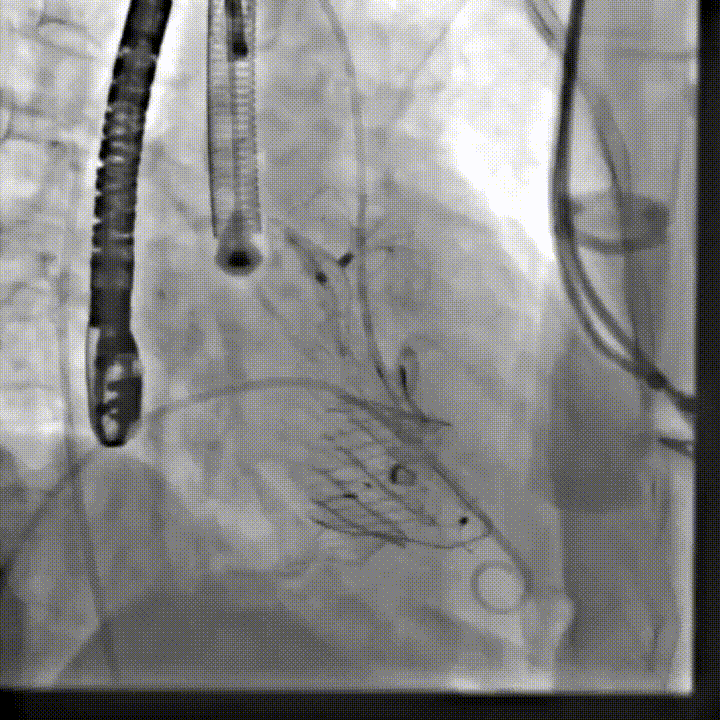

术后造影